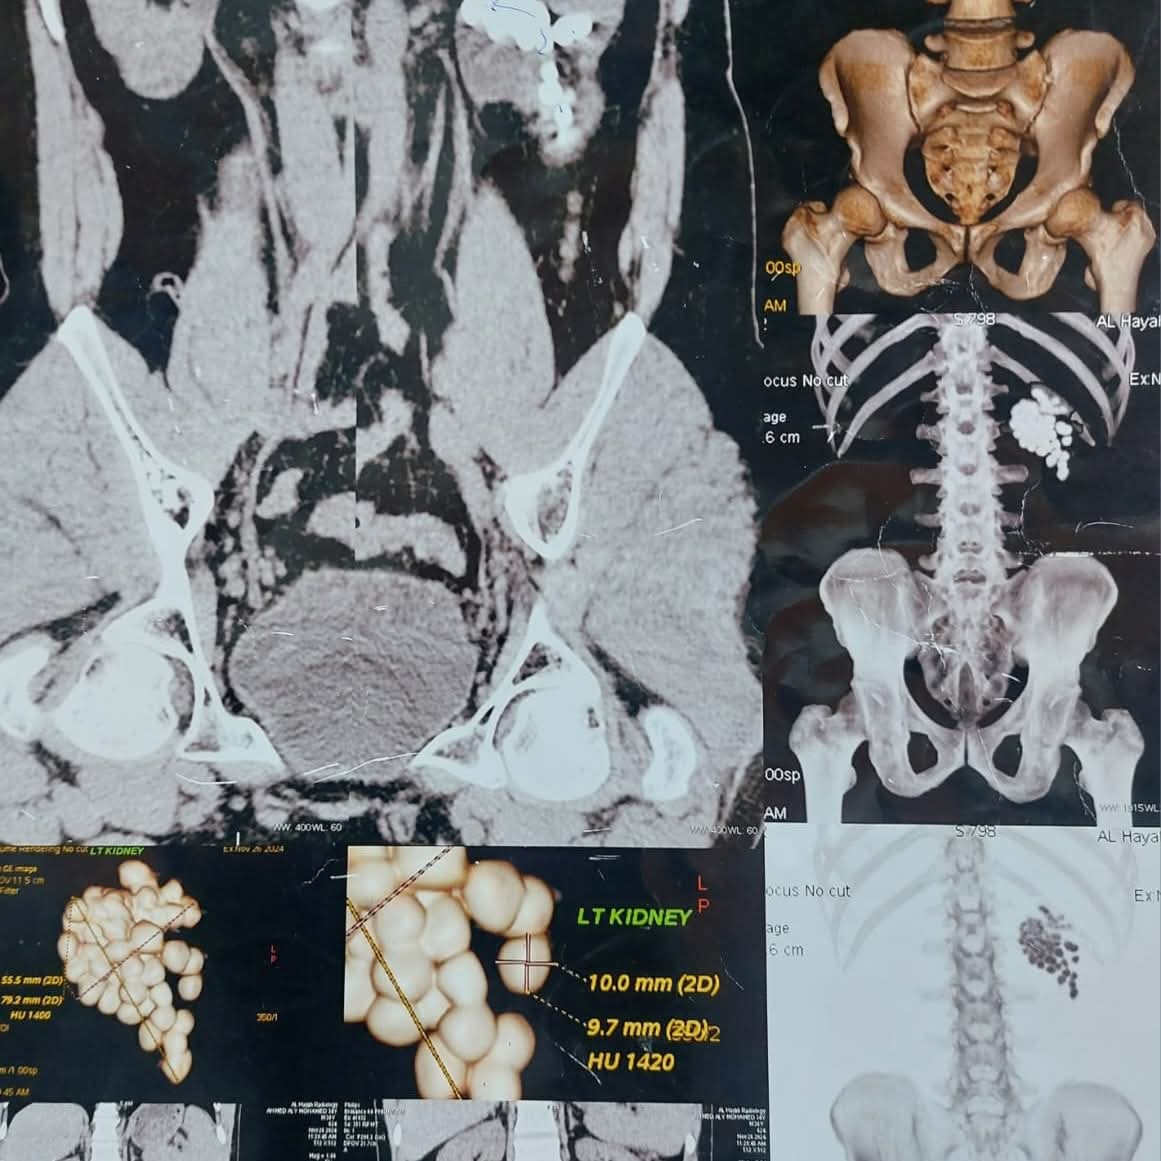

أعلن الدكتور حجاجي منصور، المدير التنفيذي لمستشفيات قنا الجامعية، نجاح فريق طبي متخصص بمستشفى المعبر الجامعي في إجراء عملية دقيقة لاستخراج 58 حصوة من الكلية اليسرى لمريض يبلغ من العمر 40 عامًا، وذلك باستخدام أحدث تقنيات مناظير الكلى المتقدمة.

وأوضح الدكتور مصطفى عبدالرازق، رئيس قسم المسالك البولية بمستشفى قنا الجامعى، بأن المريض وصل إلى المستشفى وهو يعاني من آلام متكررة وارتفاع في نسبة الأملاح، وبعد إجراء الفحوصات اللازمة تبيّن وجود عدد كبير من الحصوات المتجمعة في حوض الكلية اليسرى، مما استدعى التدخل الجراحي الفوري للحفاظ على سلامة الكلية.

وتابع عبدالرازق، وتم تجهيز المريض للعملية وإجراء التخدير العام، ثم بدأ الفريق الطبي العمل بتقنية منظار الكلية عن طريق الجلد، وهي من أحدث الأساليب التي تسمح بإزالة الحصوات الكبيرة والمتعددة بدون فتح جراحي، وتم عمل فتحة جراحية صغيرة لا تتجاوز سنتيمترًا واحدًا للوصول إلى الكلية، ثم تفتيت الحصوات باستخدام تقنيات التفتيت الهوائي والليزر تبعًا لطبيعة كل حصوة.

وأشار رئيس قسم المسالك البولية بمستشفى قنا الجامعى، إلى أن العملية استغرقت ساعتين، تمكن خلالها الفريق الطبي من استخراج الحصوات كاملة مع التأكد من تنظيف حوض الكلية تمامًا لمنع تكرار المشكلة مستقبلًا، كما تم وضع أنبوب تصريف مؤقت لضمان خروج السوائل بشكل آمن بعد العملية، وخرج المريض من غرفة العمليات في حالة مستقرة، بينما تمت متابعة علاماته الحيوية داخل الإفاقة، وسط تحسن ملحوظ في حالته العامة ووظائف الكلى.